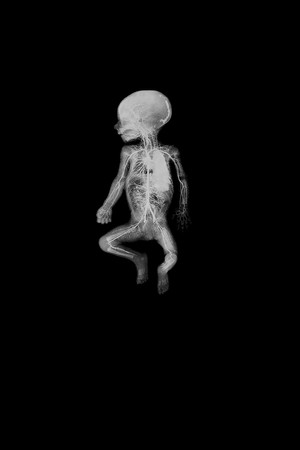

An extraordinary adventure through the interior of the human body; or the discovery of an alien landscape of unprecedented beauty.